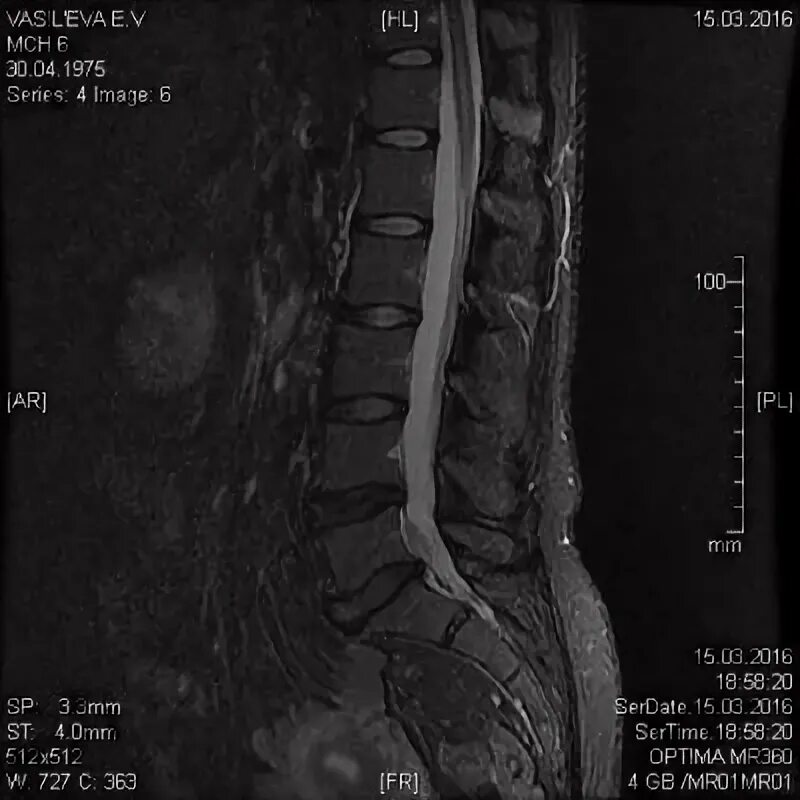

Диффузная протрузия диска l5 s1